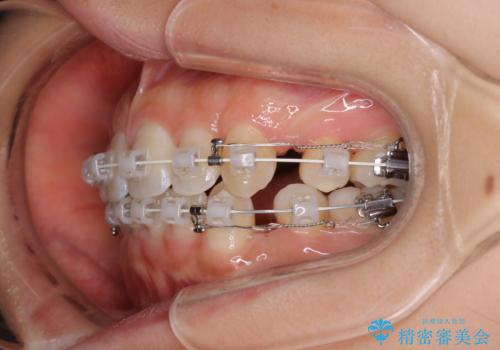

- 審美装置

- 口元をさげたいという主訴で来院されました。4番の歯を4本抜歯し、審美装置にて治療をしました。

抜歯をしたことで口元の突出感が改善しました。約2年を予定していた矯正ですが、約1年という短い期間で終了できました。